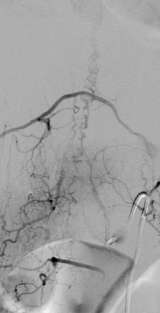

Unlike the vascular malformation on or in the spinal cord, dural or epidural AVFs (Figure 2) are an acquired condition, and are commonly discovered in mid 50s males. The symptoms include progressive weakness and numbness in the lower extremities, bowel bladder disturbance, back pain, and sexual dysfunction.

MRI and CT can detect spinal vascular malformations. However, spinal catheter angiography is oftenrequired to further classify the lesion. Making an accurate diagnosis / classification is the first step to compose the best management plan for the lesion.